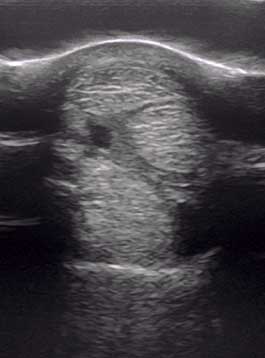

Die Ultraschalldiagnostik setzen wir in der Orthopädie, der Gynäkologie, der Inneren Medizin und auch der Augenheilkunde ein.

Im Rahmen einer orthopädischen Untersuchung können wir zum Beispiel Sehnen, Sehnenscheiden oder Gelenke schallen und hierbei den Zustand der einzelne Strukturen beurteilen.